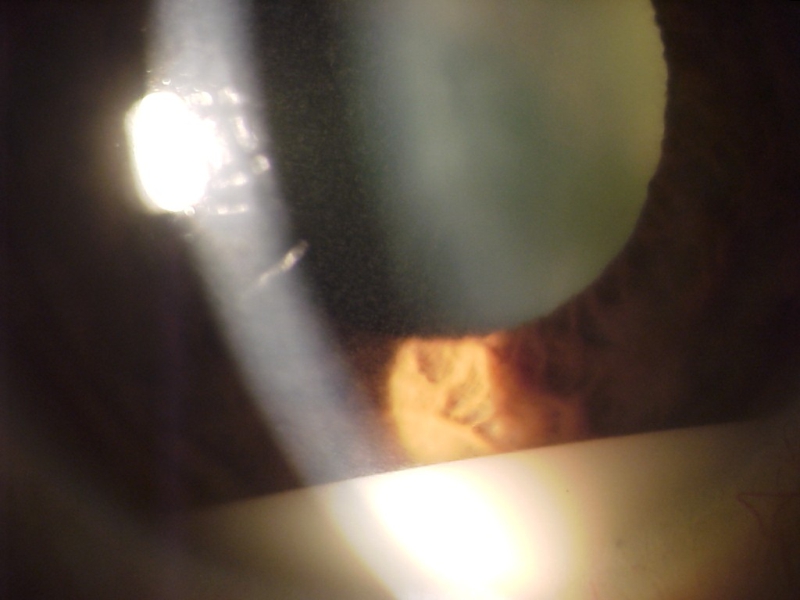

En la exploración biomicroscópica de la endoftalmitis hallaremos tyndall en cámara anterior, que puede ser proteico (flare), celular (Figura 1) y habitualmente es mixto.

Figura 1. Imagen en la lámpara de hedidura del flare celular en cámara anterior.